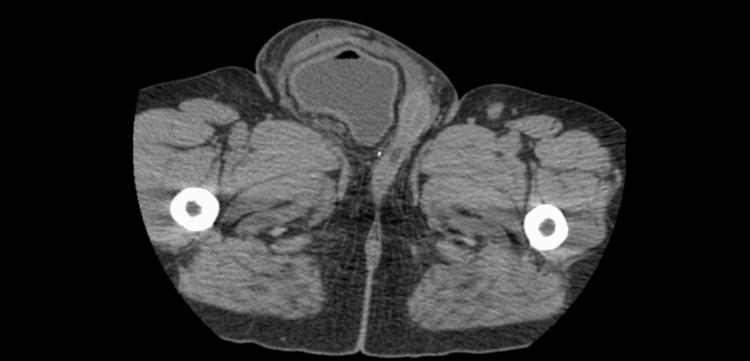

Inguinoscrotal hernias involving the urinary bladder are exceedingly rare, constituting a small subset of inguinal hernias. We present a case of a 47-year-old male with long-standing scrotal enlargement and obstructive uropathy due to complete herniation of the bladder with ureteric involvement. Diagnostic imaging confirmed the condition. Following an open laparotomy, the bladder was reduced, and a modified Bassini technique with orchiopexy was used for repair. Recurrence of the inguinoscrotal hernia with evidence of the bladder in the scrotal sac required additional surgery. This case underscores the rarity, diagnostic complexity, and potential complications of inguinoscrotal bladder hernias. Specialized surgical techniques and a multidisciplinary approach are crucial for successful management, especially in cases of complete bladder herniation. Future considerations should include innovative approaches to enhance primary repair outcomes for extensive hernias involving the bladder.

累及膀胱的腹股沟阴囊疝极为罕见,是腹股沟疝中的一小部分。我们报告一例47岁男性,因膀胱完全疝出并累及输尿管,长期阴囊肿大并患有梗阻性尿路病。诊断性影像学检查证实了病情。在进行开放剖腹手术后,将膀胱回纳,并采用改良的巴西尼技术加睾丸固定术进行修复。腹股沟阴囊疝复发且阴囊囊中出现膀胱迹象,需要再次手术。该病例凸显了腹股沟阴囊膀胱疝的罕见性、诊断复杂性和潜在并发症。专门的手术技术和多学科方法对于成功治疗至关重要,尤其是在膀胱完全疝出的病例中。未来的考虑应包括创新方法,以提高涉及膀胱的广泛性疝的一期修复效果。